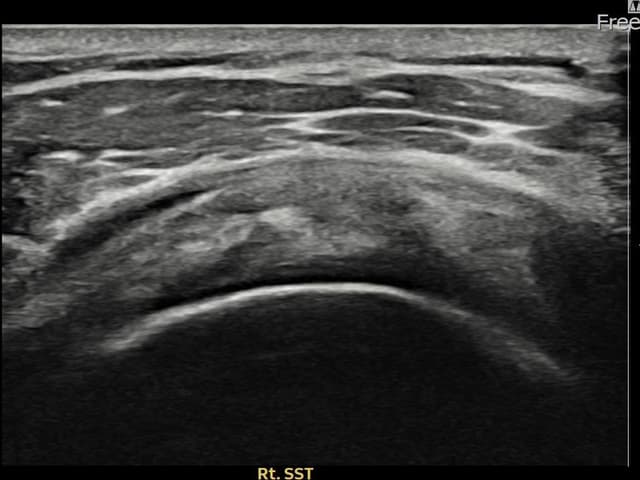

[経過期間: 24.03.21~24.05.29]

[縫縮術] 超音波検査にて右 견갑하근건 部分断裂(8mm × 3mm (腱厚の約32%欠損))を確認。縫縮術施行後、腱の連続性が回復し、日常生活に復帰されました。